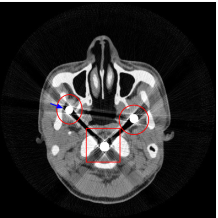

Figure 8 shows the reconstructed cerebral phantom from different methods. We highlight some regions with more distinct differences with red contours. Since the cerebral phantom contains more textures, it is more challenging than the NCAT phantom. The pros and cons of these methods are mostly the same as the previous example. However, we note that the reconstructed image from TV-FADM shown in Figure 8(e) has severe artifact, which is due to the well-known staircase artifact of TV regularization. We found that TV-FADM is relatively sensitive to the choice of its parameters. It is not easy to balance between sharpness of image features and metal artifacts reduction. The soft tissue around metal components is also not well preserved by the NMAR method as indicated by the blue arrow in Figure 8(d). Furthermore, the circled areas in Figure 8(d) show that there are still some artifacts around the metal. Same as the NCAT phantom, the proposed re-weighted JSR model has the best overall performance. Notice that the intensity of metals in Figure 8(d) and 8(f) seems lower than the rest of the reconstructed images. This is because we set the intensity of the metal components in the segmentation with the same mean value as that of bones. Increasing the value of metal components of can increase the intensity of metals in the reconstructed images, whereas it also introduces more artifacts around the metals.